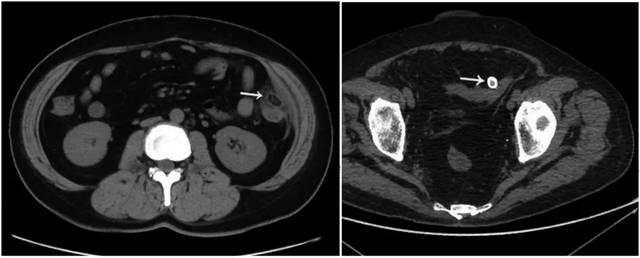

前图为肠脂垂炎发病期,后图为肠脂垂脱落发生的钙化(在影像学中,该变大钙化称为“腹腔鼠”),小腹淋巴在哪个位置图片。